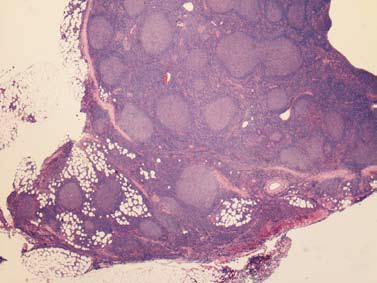

如果沒有可疑症狀,則需要做鼻咽喉內窺鏡檢查。要是發現頭頸部有惡性腫瘤(圖一是內窺鏡檢查,可見鼻咽癌),需要取組織做病理確診,然後再施以針對性治療。如果鼻咽喉內窺鏡檢查沒有發現腫瘤,需要做頸部超聲波檢查,包括腮腺、頜下腺、甲狀腺。如發現可疑病變,可進一步用超聲波導引抽取細胞病理確診(圖二是超聲波檢查,圓點所示為甲狀腺癌)。如果超聲波檢查沒有找出病原,需用超聲波導引抽取淋巴細胞做病理分析。如果淋巴細胞病理分析結果仍然未能確診,便需做手術拿取淋巴做病理切片分析,確診後便可進行針對性治療(圖三是頸淋巴癌的病理切片)。

圖三